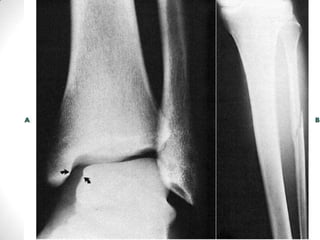

• MEDIAL MALLEOLUS

FRACTURE AND

ASSOCIATED DISTAL

FIBULA FRACTURE.

AP Ankle. Note the

medial malleolus fracture

(arrowhead) and an

oblique fracture of the

distal fibula, along with

lateral displacement of

the talus. The linear

subchondral radiolucency

in the talar dome

(arrows) is a radiographic

sign for an intact blood

supply to the talus

(Hawkin’s sign), which

represents the

unlikelihood of

complicating avascular

necrosis.